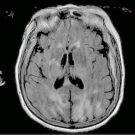

An 86-year-old woman presented to our institution from an outside hospital for management of altered mental status.

12/13/2019